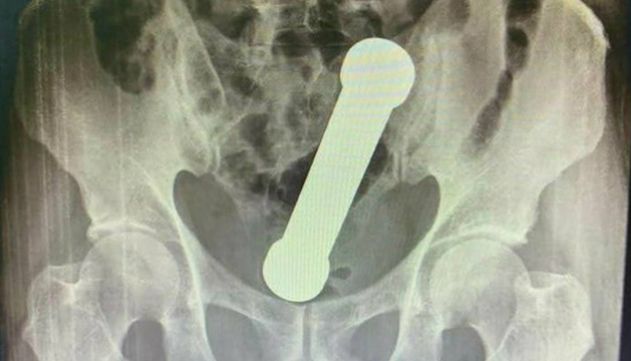

Com dores de estomâgo e dificuldades de evacuação, o homem de 57 anos procurou um hospital, onde tirou radiografias. Ao examinar as imagens, os médicos se depararam com um peso de academia de 2 quilos dentro do paciente.

Com o título de 'Manejo de corpo estranho retal incomum', o artigo descreve em detalhes os procedimentos feitos para extrair o haltere de 20 centímetros do corpo do homem.

Peso tinha cerca de 20 centímetros

Sob o efeito de anestesia, o paciente foi levado para o centro cirúrgico e teve o objeto retirado de seu corpo manualmente, sem o auxílio de instrumentos como pinças.

Ele ficou hospitalizado por mais três dias, mas não apresentou complicações e foi liberado.